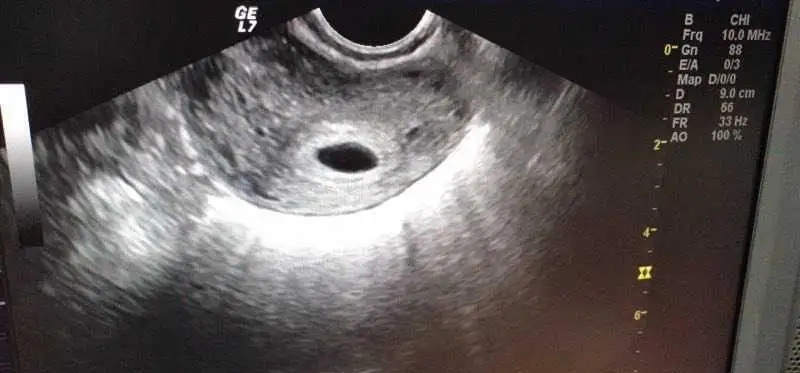

此外,这个阶段还要注意预防空囊,有时候HCG很高,但是没有卵黄囊,或者胎芽很小,也属于空囊的一种,所以单纯看HCG翻倍情况判断胚胎情况也是不准确的。